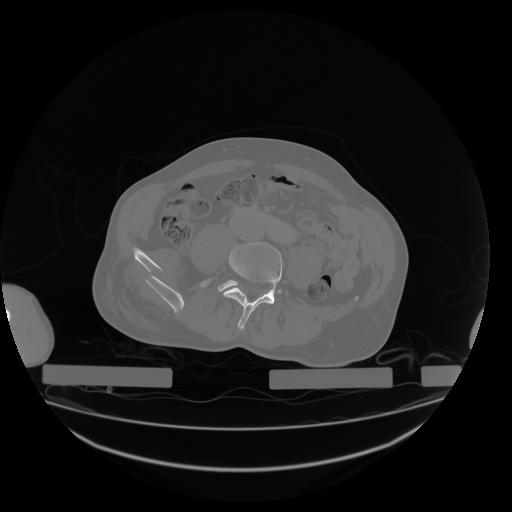

27 CUERPO,CE,Axial,3.0,CUERPO,,